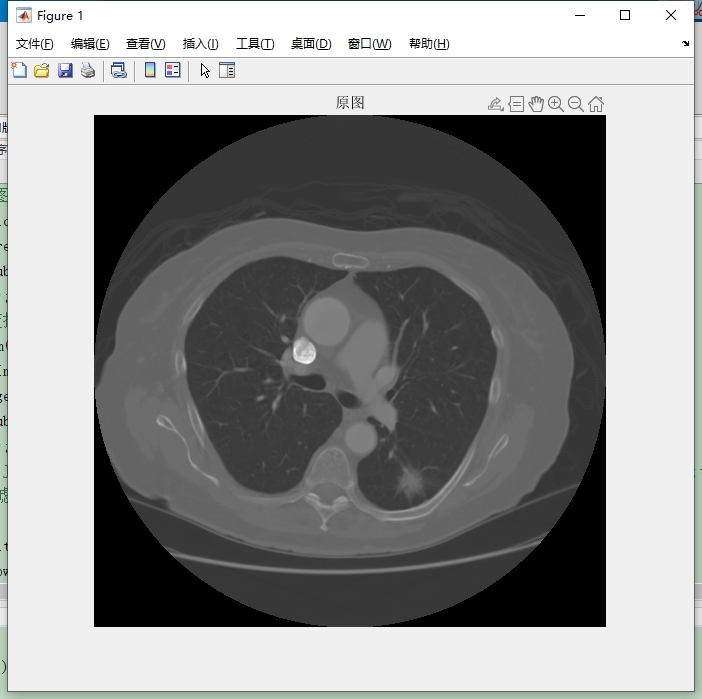

1. 读取图像

首先要读取原始dicom格式的CT图像。在Matlab里,我们可以使用 dicomread 函数轻松搞定。代码如下:

% 读取dicom图像

img = dicomread('your_dicom_file.dcm');

% 显示图像

imshow(img, []);

% 绘制灰度直方图

imhist(img);

代码分析:第一行,dicomread 函数接收dicom文件路径作为参数,读取图像数据并赋值给 img 变量。第二行,imshow 函数负责显示图像,[] 在这里的作用是让Matlab自动根据图像数据调整显示的灰度范围。第三行,imhist 函数绘制图像的灰度直方图,帮助我们直观了解图像灰度分布情况。